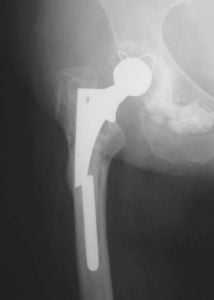

Диагностика нестабильности протеза

При наступлении первых симптомов нестабильности эндопротеза тазобедренного сустава либо до появления таковых не будет лишним пройти курс диагностических мероприятий. Врач назначит следующие виды обследования:

- рентгенологическое исследование тазобедренного сустава;

- проведение анализа состояния костной ткани и ее плотности с помощью метода денситометрии;

- анализ процессов метаболизма в костной ткани.

В некоторых случаях назначение перечисленных выше мероприятий происходит сразу же после хирургического вмешательства. Особую опасность представляет изначальное наличие у пациента остеопороза, так как именно данная особенность костной ткани может спровоцировать нестабильность протеза после установки.